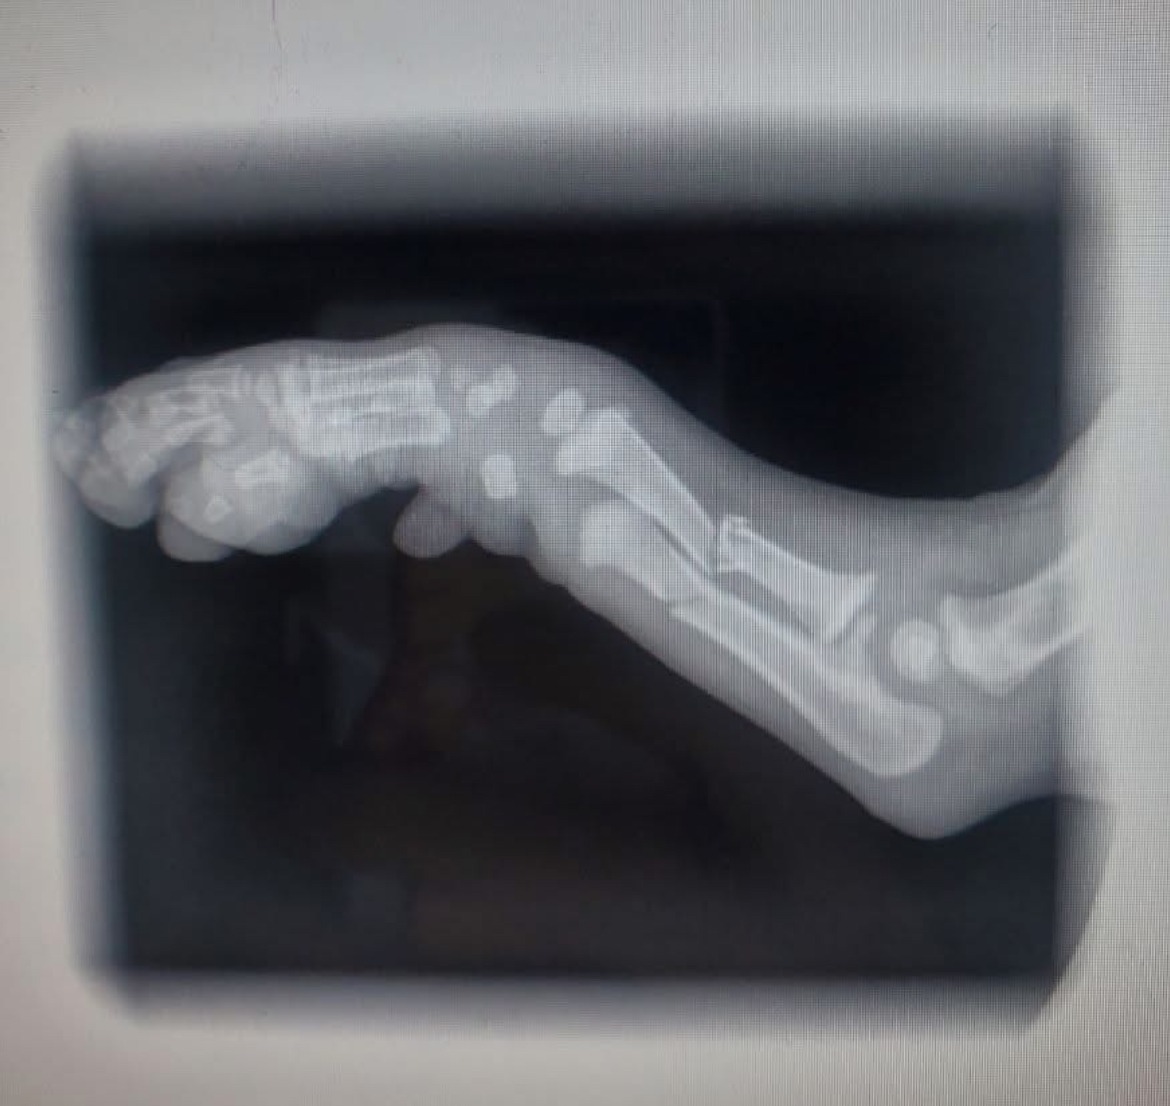

But one heartbreaking day, little Panda let out a cry no one could ignore… Rushed to the vet, we learned his tiny arm (ulna & radius) were broken. Our amazing orthopedic team quickly stepped in to perform an extensive surgery, where they were able to place a bone plate in. Thankfully the break wont effect his growth plates! Now Panda wears a cast as he begins his healing journey.